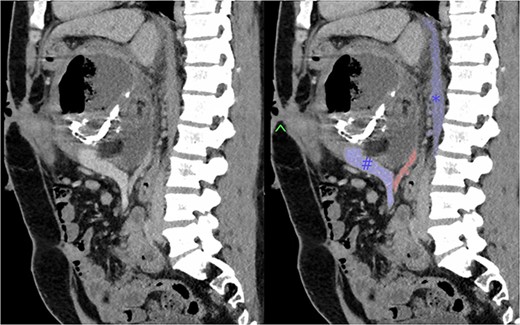

Subsequently, the patient developed severe abdominal pain and a computed tomography (CT) demonstrated possible impending perforation of the teratoma. Emergency laparotomy was performed. The teratoma was found posterior to the neck of the pancreas extending retroperitoneally behind the lesser sac. The portal structures and pancreas were attenuated and stretched over the lesion. Both the superior mesenteric vein (SMV) and inferior mesenteric vein were densely adherent to the teratoma. The superior mesenteric artery (SMA) was not able to be visualized (Fig. 1). An initial attempt was made at resection of lesion. However, when beginning to mobilize the lesion it was felt that, in order for a complete resection, at least a total pancreatectomy with portal vein reconstruction was to be required. However, due to the fact that it may not be possible to resect the lesion from the SMA or the possibility that the portal vein and SMV could not be anastomosed, radical resection was abandoned. Instead, a debulking of the mass was performed with drainage of perforated cystic contents from the abdomen.

Sagittal section of pre-operative CT with portal venous contrast showing the lesions relationship to major vascular structures of the abdomen. Labels: ^ - fistula opening, blue # - superior mesenteric vein, blue * - inferior vena cava, red - superior mesenteric artery.